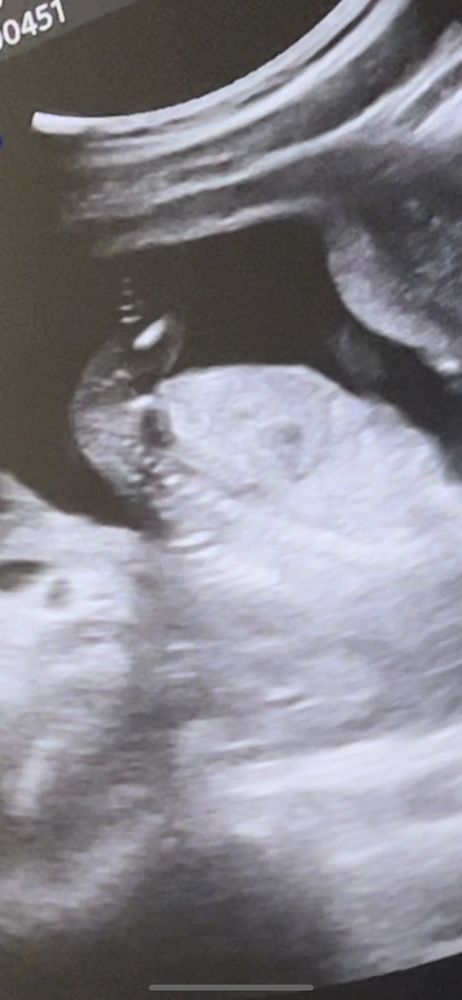

Пол 15 недель

На этом снимке я вообще не вижу бугорок (

Мне кажется мальчик 😅

Mamashka, Самое интересное, что врач говорит я ничего торчащего не увидела, когда я ей сказала, что мне показался перчик😅. Ну 25 декабря 2 скрининг, надеюсь не спрячется 😃 и на 1 скрининге сказали девочка скорее всего 😄

Виолетта, хотя знаете я присмотрелась, наверное все таки девочка, а отсвечивает может же и пуповина,поэтому показался перчик ахахаах

Eva , здравствуйте 😃 мальчик) Не зря я в 15 нед на узи увидела что-то. А Узист говорила признаков мальчика нет😅😅😅 Когда я сказала, что заметила торчок😀